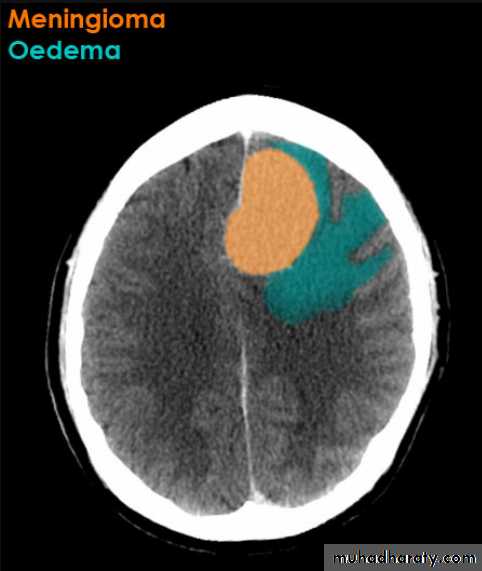

Meningioma

Benign tumor arise from the arachnid cells of the meningeal covering of the brain are most common primary intracranial neoplasm

Usually present in middle age female

it is well defined extra axial , located mainly at the convexity of the skull periphery

CT finding

meningioma presented as isodense area or slightly hyper density area with surrounded crescent of hypo density ( csf cap ) post contrast injection the lesion enhance homogeneously with enhancing Dural tail .

20 % show calcification

hyperostosis & thickening of the near by bony part of the skull & diplioc space .

it may be associated with little or no peri focal edema .

if the lesion associated with central necrosis with large perifocal edema meningio sarcoma should be excluded .